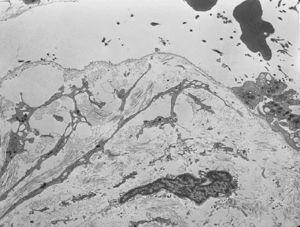

El estudio histológico de una biopsia cutánea con hematoxilina y eosina mostró separación subepidérmica sin infiltrados dérmicos. El estudio con microscopía electrónica evidenció ausencia de hemidesmosomas y rotura a través de la lámina lúcida (fig. 4).

Fig. 4.--Microscopio electrónico. Separación de la piel en la lámina lúcida. Hemidesmosomas hipoplásicos y escasos.

El diagnóstico de las epidermólisis ampollosas se confirma mediante el examen con microscopio electrónico de una biopsia cutánea de piel sana, donde se pueden observar los planos de rotura de la piel. En la EAJ-H la fisura se localiza en la lámina lúcida, donde pueden verse un número reducido de hemidesmosomas que además son hipoplásicos 12.